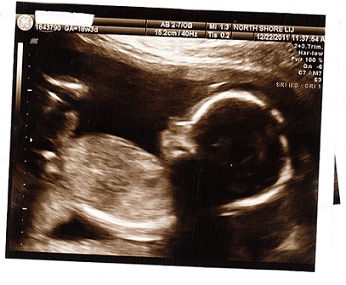

Sono experts- gender guess- Pic added

Can you guess the gender from this picture? Image Attachment(s):

Boy?! I feel like I see something down there??

Re: Sono experts- gender guess- Pic added

I'm also thinking